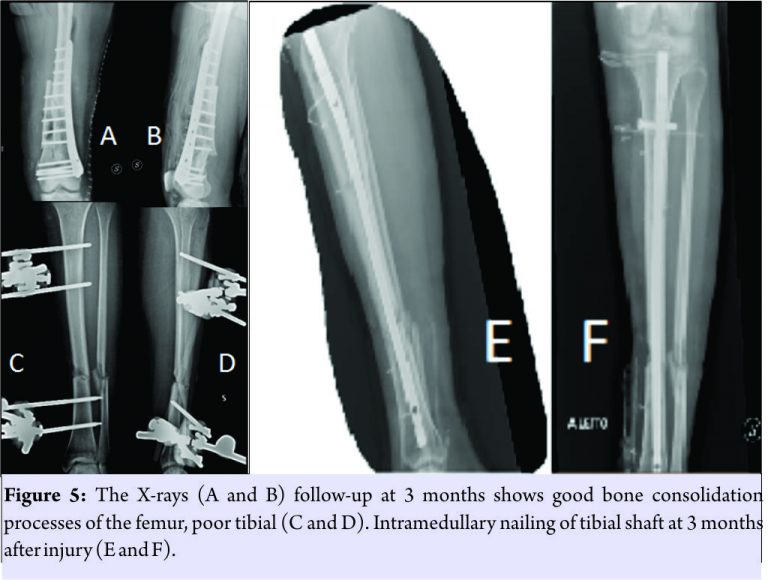

The patient was not treated surgically for the fissure of the spleen, and the resolution of the neurological picture took place after 6 days. The patient was submitted to a specific antibiotic therapy according to the protocol for the open fractures and was monitored with clinical and laboratory examinations. The 21stday post-trauma, without any clinical or laboratory signs, the patient was operated on with a less invasive stabilization system plate and screws, cortical and cancellous bone grafting allogeneic bank, and autologous stem cells taken from the iliac crest, PRP rich in leukocytes and replanting of native bone. The surgical access chosen was the lateral subvastus to preserve the perforating arteries(Fig.4). The patient was monitored with 15 days clinical follow-up, laboratory, and radiological at 1 month, 2 months, 3 months, 6 months, 12 months, 18 months, 24 months, 36 months, and 48 months. The indices used to evaluate the outcomes of this intervention were the knee injury and osteoarthritis outcome score (KOOS), the related union scorefemur (R.U.S.F.) for the femoral bone healing, and the score radiographic union score for tibial fractures (R.U.S.T.). For bone consolidation of shank, the short form 12 health survey (SF-12) for the quality of life, and the number of complications and re-operations. The patient in the immediate post-operative made active and passive mobilization of the knee until the 3rdmonth, reaching a flexion of 90°. The patient was subjected to the intervention of removal of the external fixator and intramedullary nailing of the tibia 3 months after the first surgery(Fig. 5)

The patient has walked with a partial load up to 6 months after the injury and then began to progress to a total load. At 12 months, the patient had a KOOS of 89.3 points, a SF-36 of 89.3 points, the R.U.S.T. 3 out of 3 points, and R.U.S.F. 3 out of 4 points. At 24months, the patient had an intramedullary nail removal of 100 points KOOS, 100 points SF-36, the R.U.S.T. 3 out of 4 points, and R.U.S.F. 4 out of 4 points. At follow-up at the past 36 months, a year after the removal of plaque and nail, the patient showed KOOS 100 points, a SF-36 out of 100 points(Fig. 6), and R.U.S.T and R.U.S.T 4 out of 4 points(Fig. 7). After 2 years, the patient had the tibia nail removed. The patient did not present any complications throughout the post-operative and follow-up